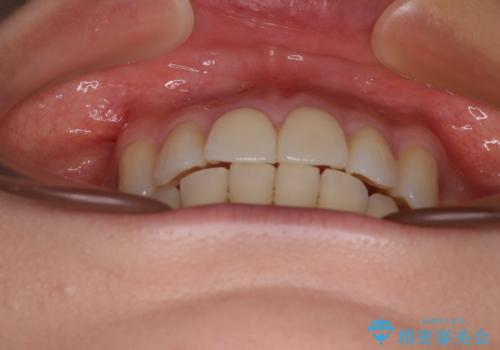

デコボコで磨きにくい歯列 ワイヤー装置での抜歯矯正で歯磨きをしやすく

- デコボコの歯列で歯磨きがしにくいことを気にして来院された患者様です。

途中むし歯が見つかり、矯正治療を行いながら迅速に対応し、何とか神経組織を保存して治療を終えることができました。